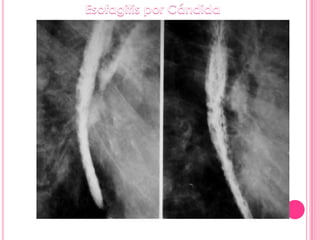

La SEGD muestra una estenosis concéntrica (flecha) en el tercio

esofágico medio en un paciente con esófago de Barret